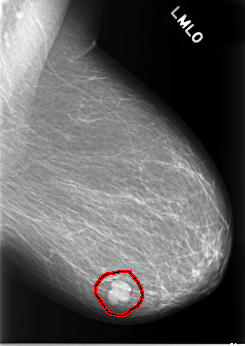

C_0082_1.LEFT_MLO

LEFT_MLO LINES 5528 PIXELS_PER_LINE 3920 BITS_PER_PIXEL 12 RESOLUTION 50 OVERLAY

FILE: C_0082_1.LEFT_MLO.OVERLAY

TOTAL_ABNORMALITIES 1

ABNORMALITY 1

LESION_TYPE MASS SHAPE LOBULATED MARGINS CIRCUMSCRIBED

ASSESSMENT 5

SUBTLETY 5

PATHOLOGY MALIGNANT

TOTAL_OUTLINES 1

BOUNDARY